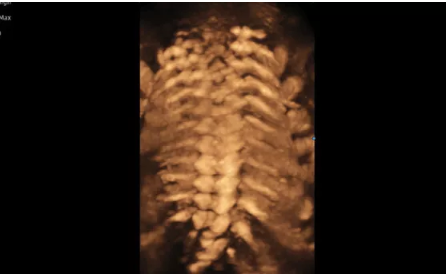

近日三星醫(yī)療推出了一款全新的母嬰超聲系統(tǒng)——Hera i 10。該款產品除了成像能力本身,人性化的座椅設計,探頭擺放位置等也是亮點之一。

Hera i 10繼承并升級了全球首款5D超聲“三星麥迪遜WS80A”的“晶體結構”成像理念,即將CrystalBeam?波束形成技術、CrystalLive?超聲成像引擎、S-Vue Transducer?視覺傳感器集于一身,提供更清晰的圖像。

3D/4D成像方面,Hera i 10通過結合先進的圖像渲染技術,著重加強了邊緣和小結構的可視化能力。